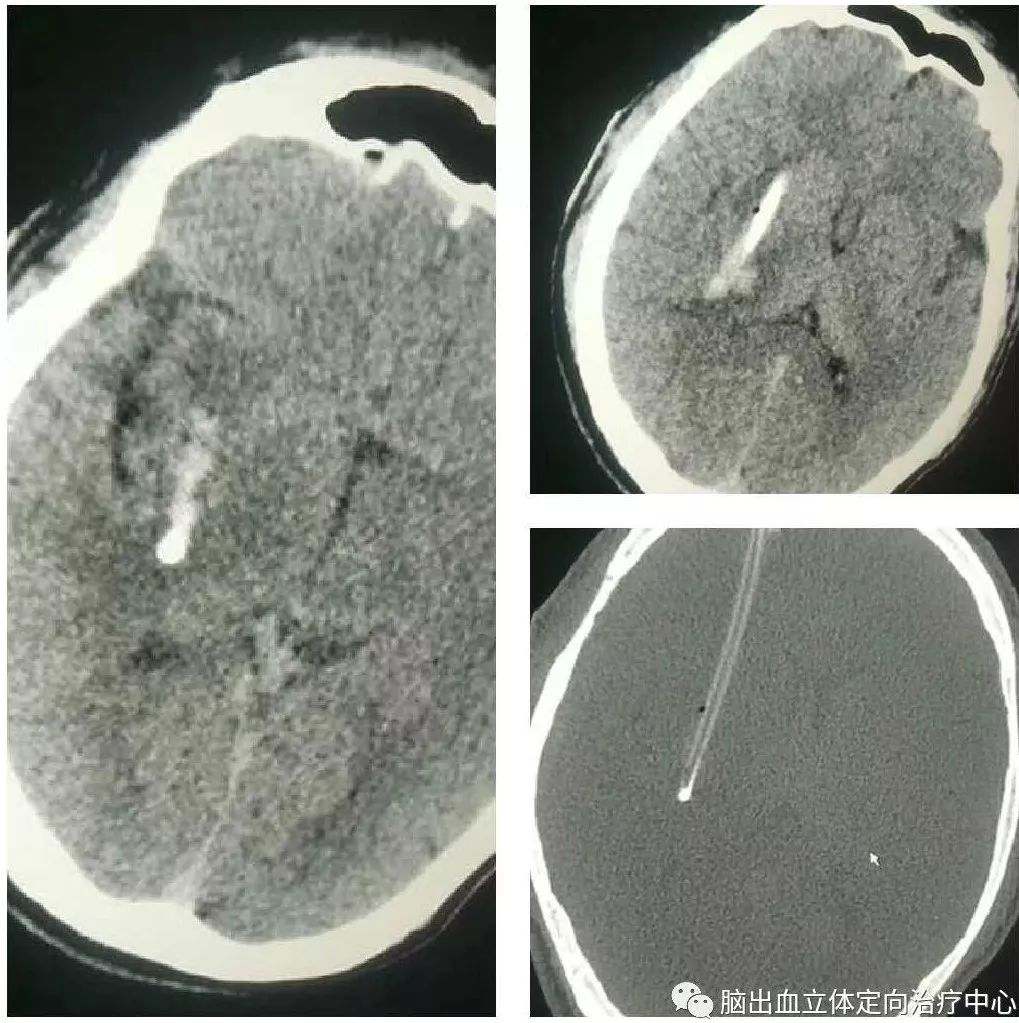

发病时CT:

第四天CT:

可见血肿呈分层现象,血肿周围水肿带明显,利用3D测量其各相关CT阈值。

利用3D技术模拟设计穿刺血肿,重建血肿体积约26ml

在3D打印导板下成功穿刺血肿,有约16ml暗褐色不凝血肿液引出,术后应用尿激酶一次,CT复查: